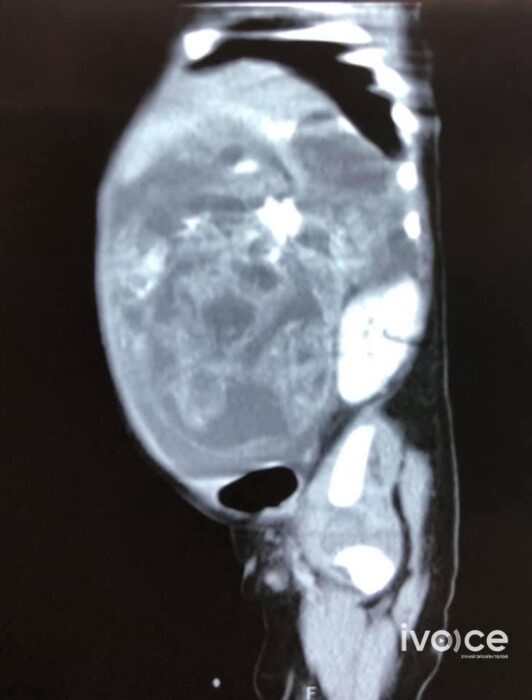

ЭХЭМҮТ-ийн Ерөнхий мэс заслын тасагт хоёр сартай хүүхдэд үр хөврөлийн гаралтай хэвлийн хавдар авах мэс засал амжилттай хийжээ. Хүүхэд 4 кг жинтэй бөгөөд хэвлийгээс нь 1064 гр хавдар авсан байна.

Хүүхдийн биеийн байдал тогтвортой, эрчимт эмчилгээний тасагт эмчлүүлж байгаа аж. Хэвлийгээс том хэмжээний хавдар авсан учраас хавдар авсан биеийн хэсэгт онгорхой зай үүссэн, цус багадалт үүсэх зэрэг хүндрэл гарах магадлалтай учир эрчимт эмчилгээний тасагт хянаж байгаа талаар мэс заслын их эмч хэлжээ.

Хүүхдийг эхийн хэвлийд ураг байхад хавдрыг оношилж, төрсөн даруйд хагалгаа хийх ёстой ч тухайн хүүхэд Хэнтий аймгаас цаг хугацаа алдаж ирснээс хэвлий томорч, суда өргөссөн, шээж бааж чадахгүй хүнд байдалтай иржээ.

Эхний шинжилгээгээр хавдар нь хоргүй гэж гарсан ч баталгаажуулахын тулд дахин эдийн шинжилгээнд өгөөд байнгаа аж. Хэрэв хоргүй бол цаашдаа эрсдэл багатай гэдгийг мэс заслын багийнхан хэлж байна.